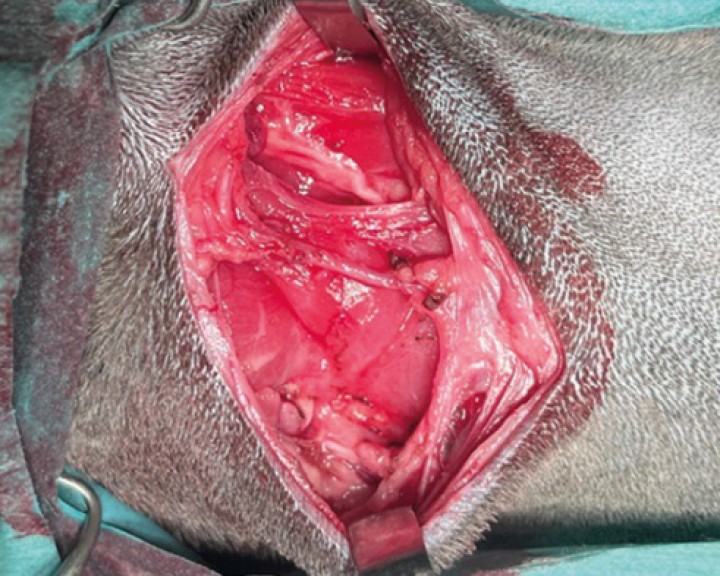

Espacio subcutáneo donde se localizaba el complejo mandibular-sublingual. Tras su completa exéresis se realiza una irrigación del plano subcutáneo con ropivacaína al 0,2 %. Se coloca drenaje de succión activa y cierre de la zona quirúrgica por planos: aposición del tejido muscular con polidioxanona 2/0 punta de aguja atraumática, aposición del tejido subcutáneo con polidioxanona 3/0 punta de aguja atraumática, sutura intracuticular con poligliconato 3/0 punta de aguja traumática.